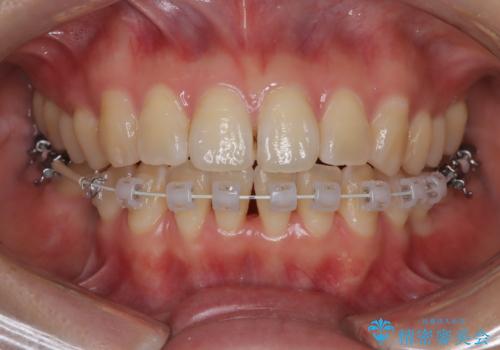

- 矯正装置

- 審美装置

- 患者様は、右下第2小臼歯(5番)の先天欠如により乳歯が残存している状態でした。

加えて、**下顎前歯部に叢生(歯のがたつき)**が見られ、審美的・機能的な改善を希望されて来院されました。

また、欠損部にインプラントを埋入するには、前後の歯の傾斜改善とスペース確保のための矯正治療が必要でした。

下顎前歯の叢生も同時に改善できるよう、全体的なワイヤー矯正による治療計画を立案しました。